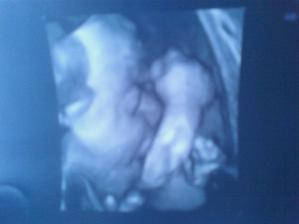

Nasa zubrienka

Pan Boh nam pozehnal malu zubrienku. Velmi sa z nej tesime a modlime sa aby, ked raz vyrastie v nase babo, bolo zdrave a krasne.